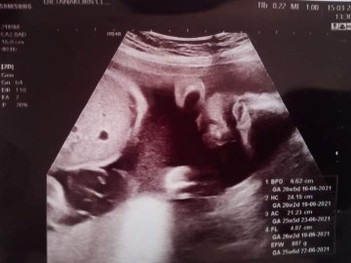

26w5d นน.887gแล้วคะดิ้นดีมากแม่น้ำหนักขึ้นมา8/9โลเลย แม่ๆน้ำหนักน้องเท่าไรแล้วค่ะ 17มิถุนายน ลูกสาว

กำหนด17มิถุนา เหมือนกันค่ะซาวด์ล่าสุดตอน26+1 น่ำหนัก942 ตอนนี้27+3แล้วจ้า